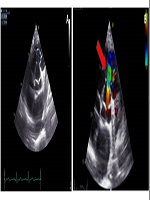

Aneurysm of Right Sinus of Valsalva: A Particular Case Report and Brief Review of Literature

LUIGI NUNZIATA, Saverio Ambrosino, Mario Volpicelli, Michele Capasso, Luigi Caliendo

International Journal of Innovative Research in Medical Science·February 14, 2023